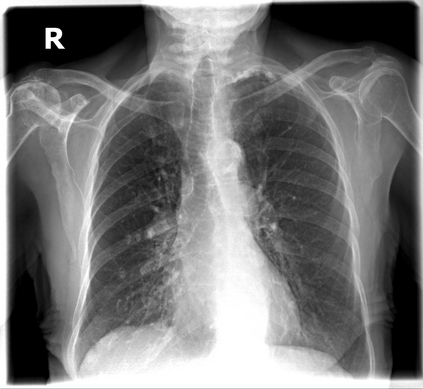

The evaluation of infectious disease processes on radiologic images is an important and challenging task in medical image analysis. Pulmonary infections can often be best imaged and evaluated through computed tomography (CT) scans, which are often not available in low-resource environments and difficult to obtain for critically ill patients. On the other hand, X-ray, a different type of imaging procedure, is inexpensive, often available at the bedside and more widely available, but offers a simpler, two dimensional image. We show that by relying on a model that learns to generate CT images from X-rays synthetically, we can improve the automatic disease classification accuracy and provide clinicians with a different look at the pulmonary disease process. Specifically, we investigate Tuberculosis (TB), a deadly bacterial infectious disease that predominantly affects the lungs, but also other organ systems. We show that relying on synthetically generated CT improves TB identification by 7.50% and distinguishes TB properties up to 12.16% better than the X-ray baseline.